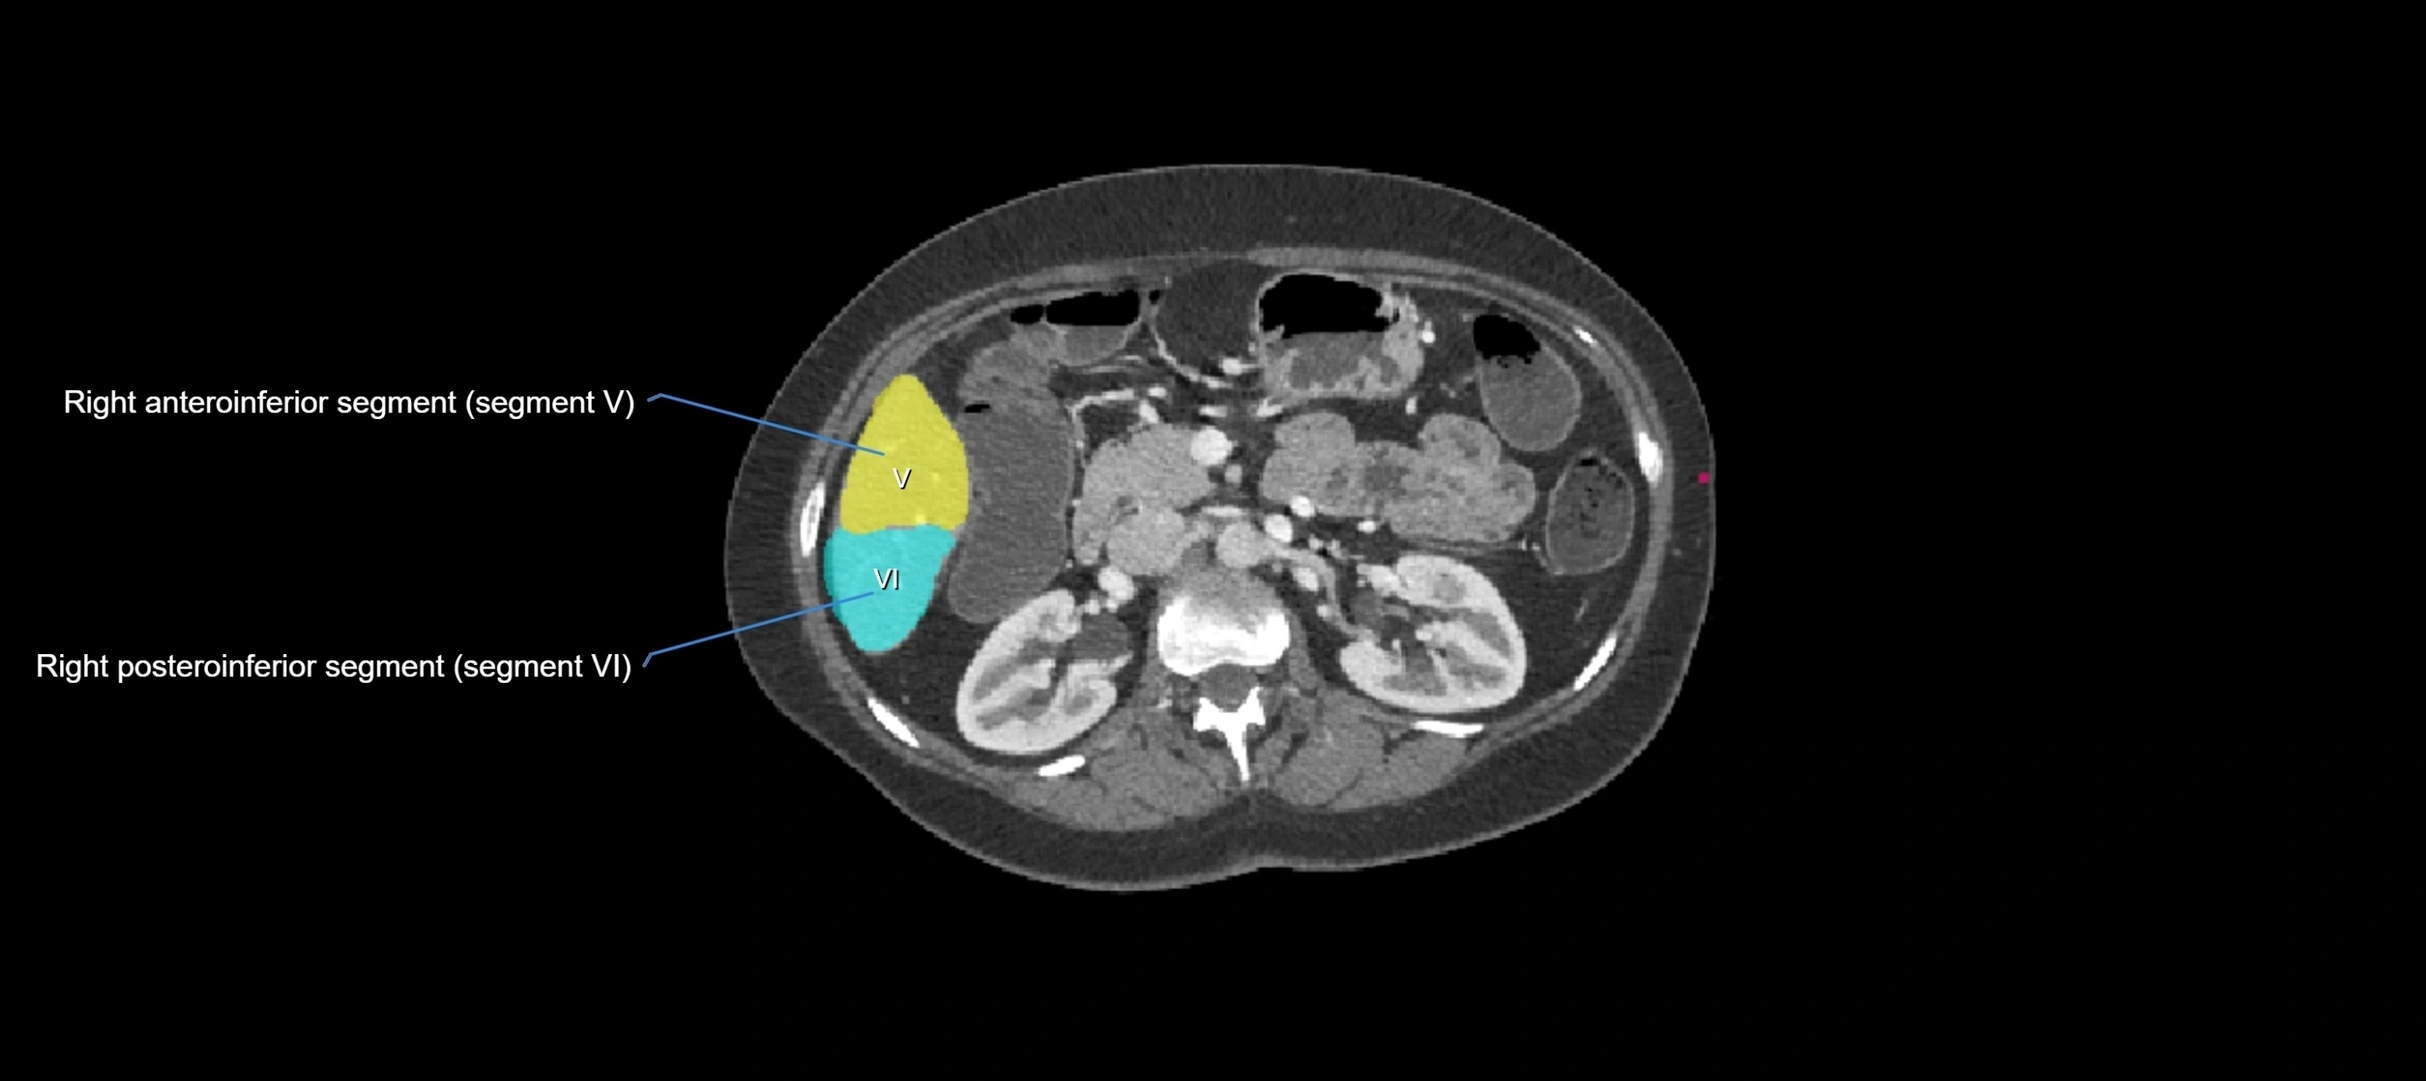

CT Image

image